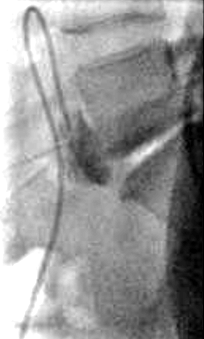

神经阻滞

SHNB 显著增强疼痛控制,降低对患者自控镇痛泵(PCA泵)的需求,并缩短住院时间

SNHB 可能使 UFE 能够在常规门诊基础上提供,且几乎100%当天出院

SHNB 的作用持续约 8 至 12 小时【Spencer EB 2013】

栓塞术后综合征在 6 至 8 小时达到高峰,其中在最初的 24 小时内不适感最为严重【Yoon J 2018】。